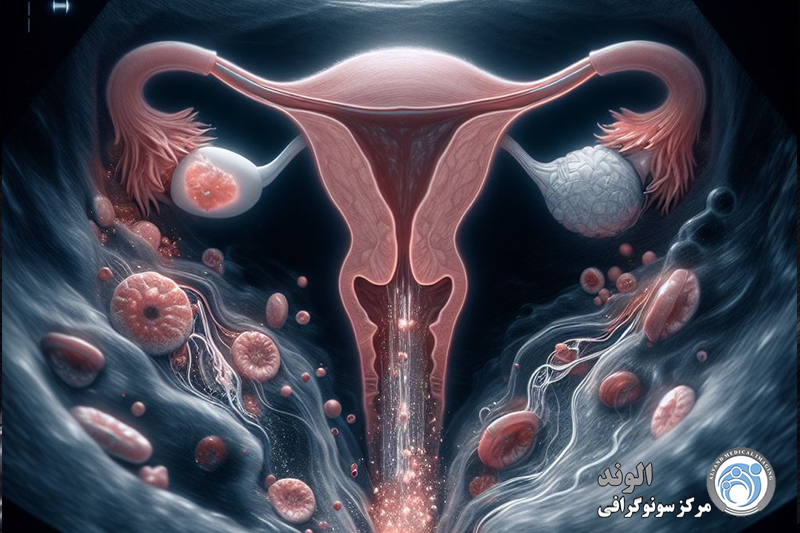

اندومتریوز؛ آندومتر بافتی است که داخل رحم را می پوشاند. اندومتریوز وضعیتی است که در آن بافتی مشابه به بافت آندومتر در خارج از قسمت رحم یافت می شود. در ناحیه لگن و شکم تحتانی (شکم) و به ندرت در سایر نواحی بدن «به دام افتاده» است. در حال حاضر مشخص نیست که چه چیزی باعث آندومتریوز می شود. عوامل متعددی وجود دارد که احتمالاً دلایل ژنتیکی، ایمونولوژیکی و هورمونی را شامل می شود.

این بیماری زمانی اتفاق میافتد که بافت مشابه با بافت داخلی رحم (آندومتر) در جایی خارج از رحم رشد میکند، معمولاً در تخمدانها، لولههای فالوپ یا سایر اندامهای لگنی. علائم آندومتریوز میتواند شامل دردهای شدید قاعدگی، درد در حین رابطه جنسی، مشکلات باروری و خونریزی غیر طبیعی باشد. با این حال، بسیاری از زنان مبتلا به آندومتریوز ممکن است بدون علائم جدی یا فقط علائم خفیف داشته باشند، که این ممکن است تشخیص بیماری را دشوار کند.

اندومتریوز یک بیماری زنان است که در آن بافتی مشابه به بافت داخلی رحم (اندومتر) در خارج از رحم رشد میکند. این بیماری میتواند به شدت دردناک باشد و مشکلاتی چون ناباروری، دردهای مزمن لگنی، و اختلالات قاعدگی را ایجاد کند. تشخیص زودهنگام اندومتریوز اهمیت زیادی دارد زیرا میتواند به مدیریت مؤثرتر علائم و بهبود کیفیت زندگی بیماران کمک کند. یکی از روشهای رایج و غیرتهاجمی برای تشخیص اندومتریوز استفاده از سونوگرافی است که به ویژه در شناسایی برخی از ویژگیهای این بیماری بسیار مؤثر است.

به ندرت، لکه های اندومتریوز در سایر نقاط بدن رخ می دهد. این می تواند باعث ایجاد دردهای غیرعادی در قسمت هایی از بدن شود که همزمان با دردهای پریود رخ می دهد.اندومتریوز باعث می شوددر طول سالیان متمادی تئوری های مختلفی برای علت آندومتریوز وجود داشته است. پوشش داخلی رحم (رحم) آندومتر نامیده می شود. یک نظریه این بود که برخی از سلول های آندومتر به خارج از رحم وارد ناحیه لگن می شوند. وقتی پریود میشوید، با ریختن به سمت عقب در امتداد لولههای فالوپ به آنجا میرسند.لکه های اندومتریوز تمایل دارند "چسبنده" باشند و ممکن است اندام ها را به یکدیگر بپیوندند. اصطلاح پزشکی برای این چسبندگی است. برای مثال، مثانه یا روده ممکن است به رحم «بچسبد». تکه های بزرگ آندومتریوز ممکن است به کیست هایی تبدیل شوند که هر ماه هنگام پریود شدن شما خونریزی می کنند. کیست ها می توانند با خون تیره پر شوند و به عنوان کیست های شکلاتی شناخته می شوند.

آندومتریوز یک اختلال رایج است که در آن بافت مشابه آندومتر در جایی که قرار نیست رشد می کند. بافت آندومتر بافتی است که در رحم رشد می کند و می ریزد. در بیشتر موارد، این رشد روی اندامهای حفره لگن و اطراف آن اتفاق میافتد. بافت در اندومتریوز مشابه بافت داخل رحم عمل می کند: رشد می کند، ضخیم می شود و سعی می کند با هر سیکل قاعدگی ریزش کند. از آنجایی که بافت راهی برای خروج از بدن ندارد، میتواند باعث چسبندگی، ندولها و ضایعاتی شود که باعث واکنش التهابی میشود. این می تواند منجر به درد و سایر عوارض مانند ناباروری شود.

آندومتر پوشش داخلی رحم (رحم) است. این بافت به طور معمول در طول چرخه قاعدگی مراحل رشد و ریزش را طی می کند. آندومتریوز زمانی رخ می دهد که آندومتر خارج از محل معمول قرار داشته باشد. اندومتریوز ممکن است در تخمدان ها، لوله های فالوپ، واژن یا سایر قسمت های رحم رخ دهد. به ندرت ممکن است اندومتریوز در شکم و ریه ها رخ دهد.

تصور میشود که خونریزی از ایمپلنتهای صفاقی باعث التهاب استریل و به دنبال آن رسوب فیبرین، تشکیل چسبندگی و در نهایت ایجاد اسکار میشود که سطوح صفاقی اندامها را مخدوش میکند و منجر به درد و آناتومی لگنی مخدوش میشود.

علائمی که در آندومتریوز مشاهده می شود به دلیل قطعات پراکنده آندومتر در حفره شکمی است. تحت تأثیر هورمون های جنسی، این قطعات تکثیر شده و خونریزی می کنند و باعث التهاب موضعی و ایجاد کیست، زخم و چسبندگی فیبری بین اندام های شکم (خارج از رحم، لوله های فالوپ، تخمدان ها، رباط های بین رحم و لگن، رکتوم می شوند). مثانه، روده ها، دیافراگم، صفاق، کلیه ها و غیره)